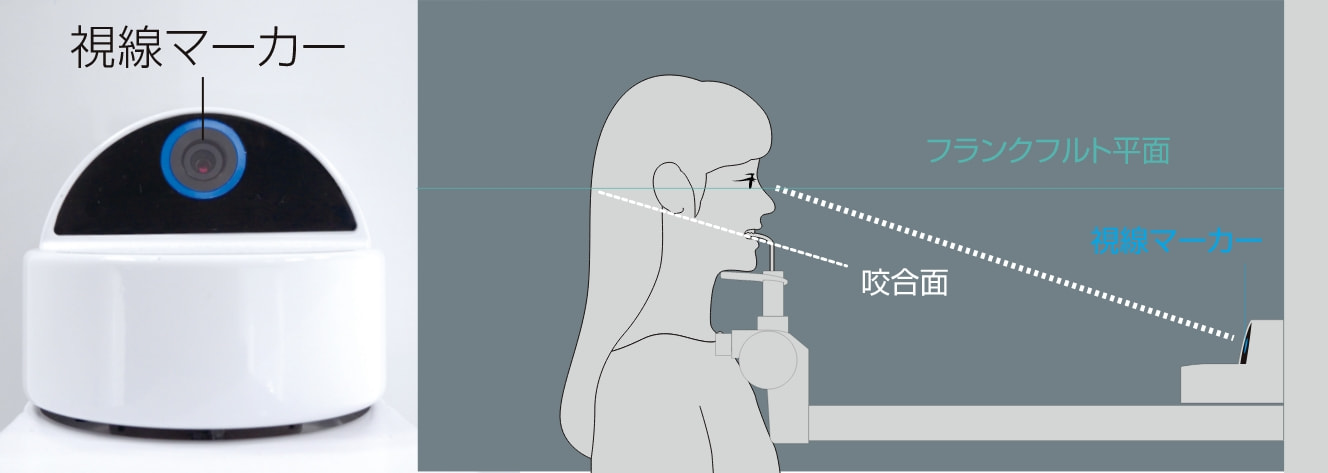

患者さんを適切な撮影姿勢へ誘導する視線マーカー

パノラマ撮影の位置付けの際、患者さんが事前に顎を引いた姿勢になる「視線マーカー」という目印を搭載しました。

12度の傾斜をつけたバイトピースを、くわえた状態で視線マーカーを見ていただくことにより、自然にフランクフルト平面が水平に近づくという工夫をしています。